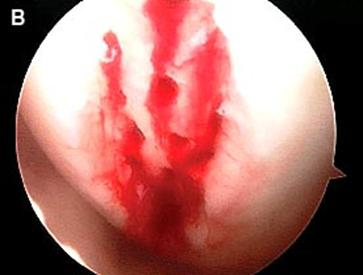

Debridarea (a, b, c).

a. b.

Fig.25.a. Debridarea. Fig.25.b. Microfracturare.